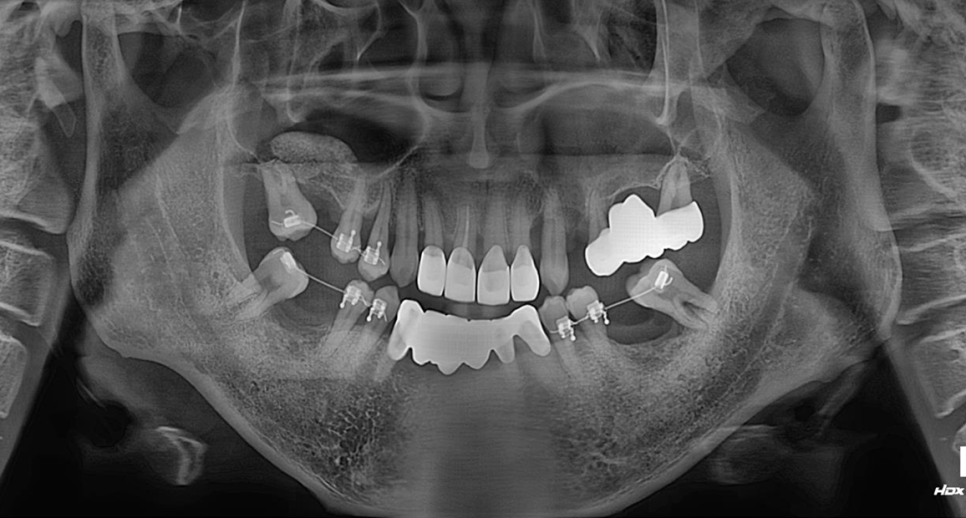

부분교정으로 쓰러진 치아들을 세우기로 했습니다.

쓰러진 치아를 세우려면

최소 4개월 이상 걸리기 때문에

기다리는 동안 상악동거상술을 해서

임플란트 심을 공간이 생기면

곧바로 식립할 준비를 해놨습니다.

양쪽 상악동 뼈가 종잇장 정도로만 남아있네요.

그렇지만 왼쪽은 기존브릿지를 그대로 사용하고

오른쪽만 임플란트를 심을 예정입니다.